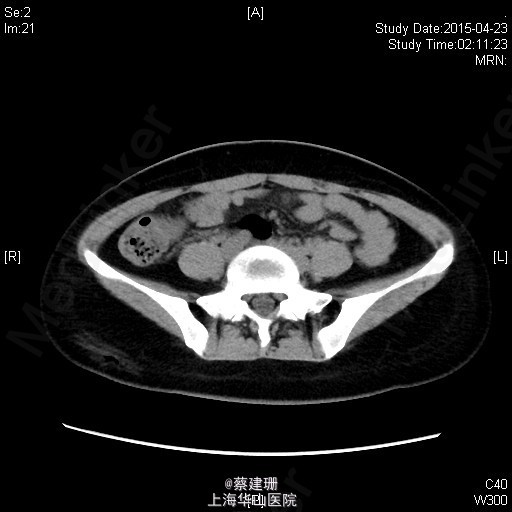

急性阑尾炎(粪石?)伴局限性腹膜炎

患者 女性 24岁,因“转移性右下腹痛一天余。”入院。患者一天前无明显诱因下出现中上腹疼痛,无恶心呕吐,无腹泻。10小时前疼痛转移至右下腹,原先中上腹疼痛缓解,无发热无腹泻。患者未予重视,后疼痛难忍于今日凌晨至我院急诊就诊,血常规示:WBC:18.63*10^9/L,我院B超示:右下腹见肠段局限性扩张,炎性病灶待排。肝胆胰脾肾未见明显异常,双输尿管未见扩张。我院CT示:阑尾增大壁增厚内见高密度影及低密度气体影,符合阑尾炎改变,盆腔少量积液。患者拒绝行急诊手术,故予以保守治疗,患者症状未缓解,右下腹疼痛加重。为行进一步诊治,收入院。

全身皮肤粘膜未见异常,无肝掌,全身浅表淋巴结无肿大。腹平坦,腹壁软,右下腹压痛,伴有肌紧张及反跳痛,麦氏点压痛(+),肝脾肋下未触及,肝肾脏无叩击痛,肠鸣音4次/分。 辅助检查:血常规示:WBC:18.63*10^9/L,N:89%。我院B超示:右下腹见肠段局限性扩张,炎性病灶待排。肝胆胰脾肾未见明显异常,双输尿管未见扩张。我院CT示:阑尾增大壁增厚内见高密度影及低密度气体影,符合阑尾炎改变,盆腔少量积液。

入院后诊断:急性阑尾炎伴局限性腹膜炎。完善相关检查,全麻下行腹腔镜下阑尾切除术。术后恢复可,伤口无明显渗出,予以出院。